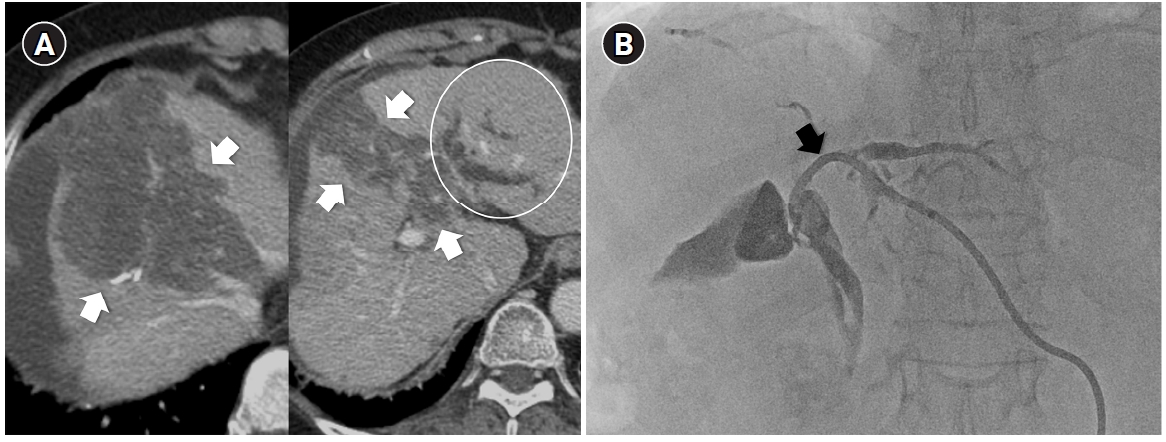

Fig. 4.

Superselective transarterial chemoembolization (TACE) for five nodular tumors in a 60-year-old man. (A) Common hepatic arteriography shows five nodular tumors. Superselective TACE was performed through tumor-feeding arteries including A1, A3, A4, A6, and A8. (B) Post-TACE fluoroscopy shows dense lipiodol uptake within the tumors without significant parenchymal deposition.

Fig. 4. Superselective transarterial chemoembolization (TACE) for five nodular tumors in a 60-year-old man. (A) Common hepatic arteriography shows five nodular tumors. Superselective TACE was performed through tumor-feeding arteries including A1, A3, A4, A6, and A8. (B) Post-TACE fluoroscopy shows dense lipiodol uptake within the tumors without significant parenchymal deposition.